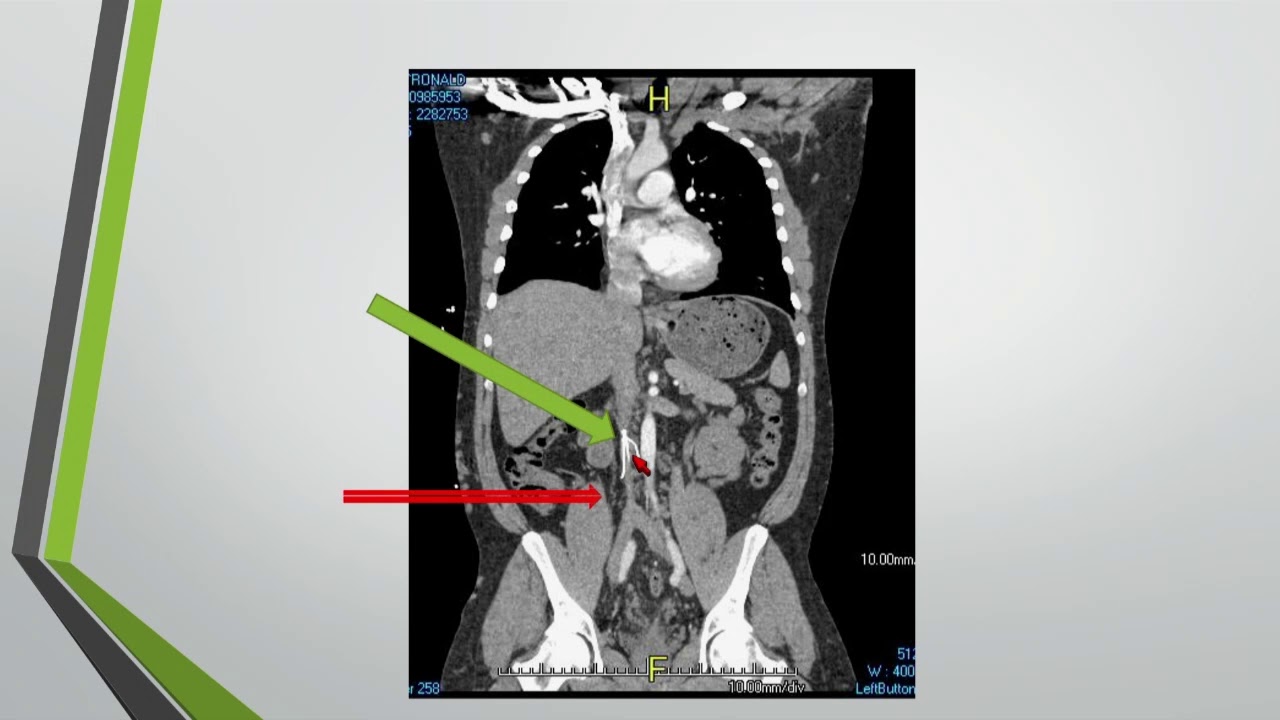

Therapeutic Options to Dialyze the Patient With Central Venous Occlusion

(Visit: http://www.uctv.tv) Robert Harland, MD. Professor of Surgery. University of Alabama. Recorded on 04/15/2016. Series: "UCSF Vascular Surgery Symposium" [Health and Medicine] [Show ID: 30902]